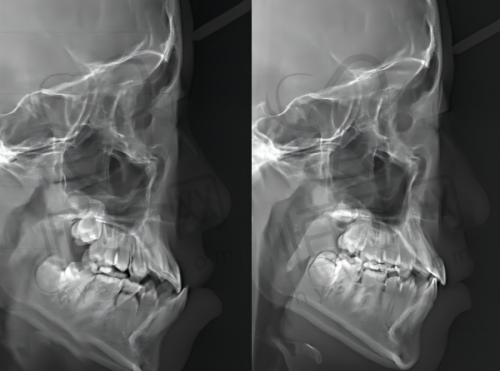

宁德福鼎市优博仕口腔门诊部配备了精良的诊疗设备,为正确诊断和有效治疗提供了有力保护。其中,德国卡瓦CT精细诊断系统是一大亮点。该设备能够提供高精度的口腔影像,帮助医生清晰地了解患者口腔内部的结构和状况,为制定治疗方案提供正确的依据。通过CT扫描,医生可以更精细地确定种植牙的位置、角度和深度,提高种植手术的成功几率。同时,对于牙齿矫正等项目,也能更正确地分析牙齿的排列和咬合情况,为制定个性化的矫正方案提供有力支持。